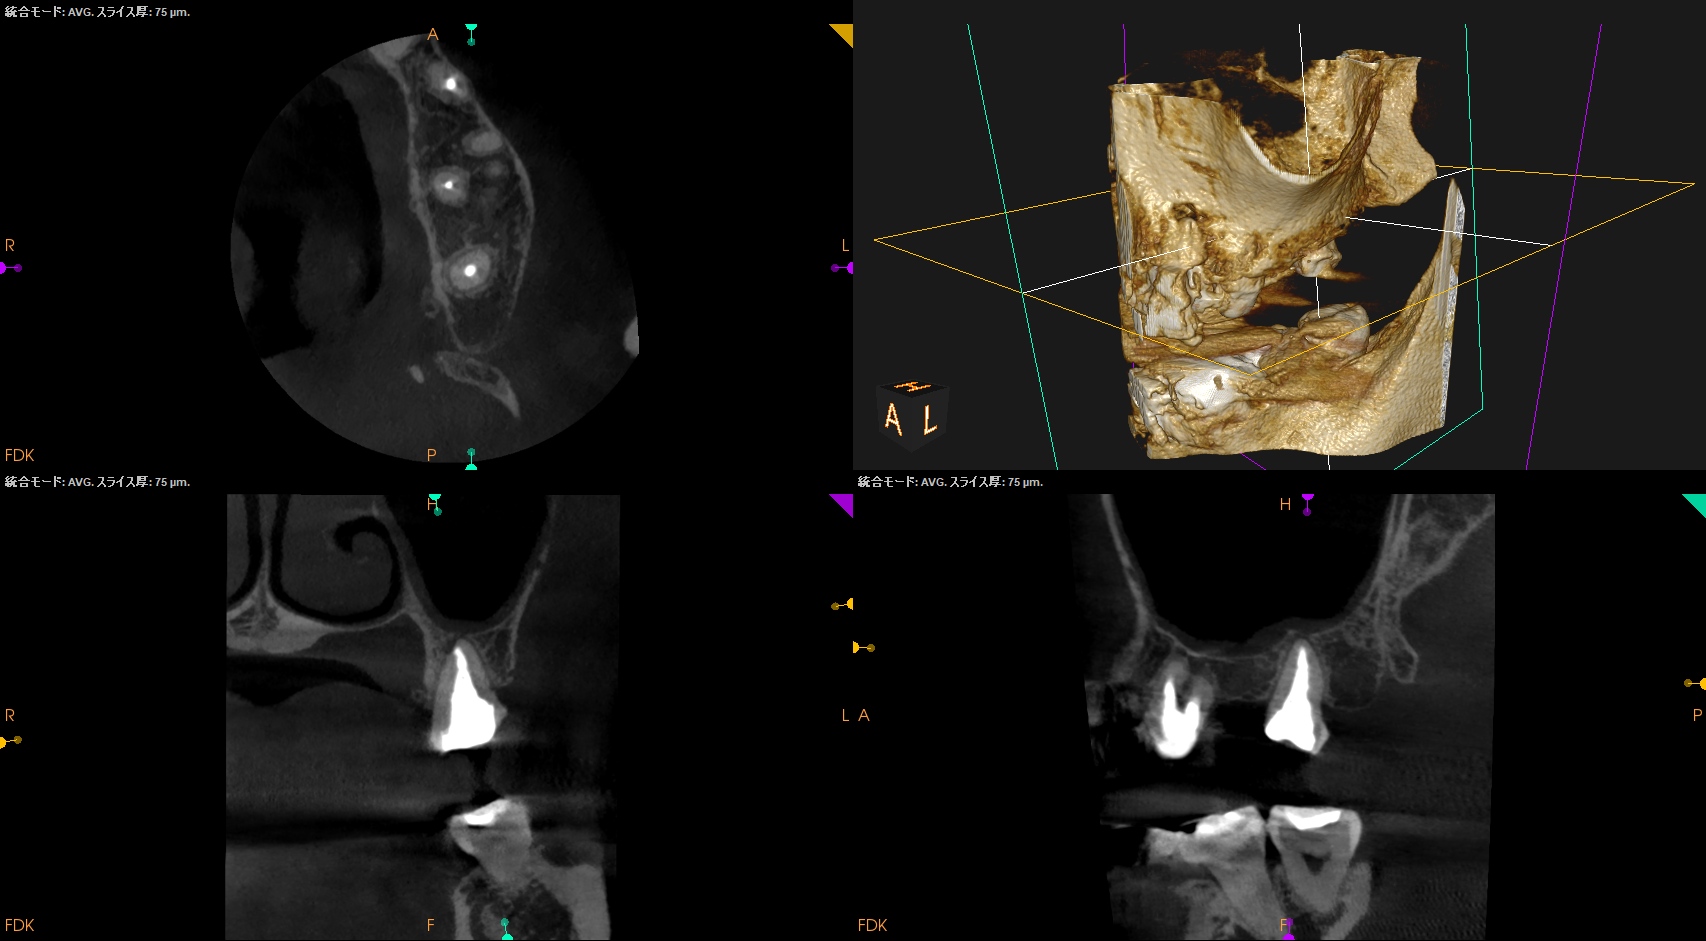

CBCT(2024.7.1)

#3

MB

DB

P

MB,DB,Pと3根全てに病変がある。

しかも形成が不完全だ。

再根管治療が濃厚である。

#14

MB,DBには病変がないが、Pに存在する。

これは頭が痛い。

パラタルフラップも困難なケースだからだ。

#16